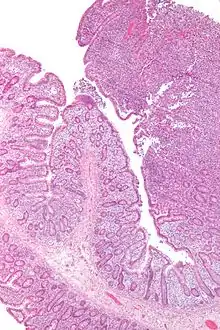

![]() صورة مجهرية للمفوما تائية الخلايا مرافقة للاعتلال المعوي (أعلى يمين الصورة). نوع من اللمفوما تائية الخلايا. صبغة H&E. صورة مجهرية للمفوما تائية الخلايا مرافقة للاعتلال المعوي (أعلى يمين الصورة). نوع من اللمفوما تائية الخلايا. صبغة H&E. | |